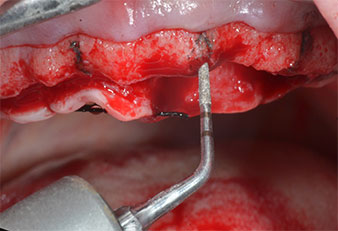

Compte tenu de la dureté relative de l’os (D2) à cet endroit, les sites recevant des implants de 10mm de long aux régions 11 et 21 ont été finalisés à l'aide d’une fraise de 4mm de diamètre, associée à un contre-angle chirurgical W&H WS-75 L, au moteur d'implantologie Implantmed de W&H ainsi qu’au module Osstell ISQ de W&H. En revanche, en raison de leur structure osseuse molle, les sites postérieurs ont été préparés en vue de l’obtention d’un diamètre final de 3mm à l'aide de l’insert Piezomed I3P. Les implants ont enfin été posés par voie transgingivale (Flap Less) pour obtenir l’ostéointégration dans un délai de trois mois (Figures 6-10). L'appareil existant a été maintenu sur quatre implants provisoires (Fig. 8).